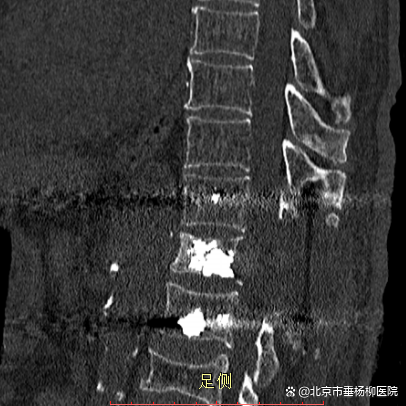

原来在一年前,黄老因罹患肾脏肿瘤行左肾切除术,但术后病理不详。脊柱外科(骨四科)主任姜树东在得知这一情况后,立即为患者完善胸腰椎核磁共振检查。结果提示T12椎体骨质破坏,结构不完整,向后压迫硬膜囊,椎管狭窄,脊髓受压;周围软组织肿胀;考虑病理性骨折(T12),脊柱转移瘤可能性大。随后,再行T12椎体穿刺活检术。同时患者家属提供了患者的既往病历:左肾肿瘤符合透明细胞癌。

椎骨活检病理结果显示:(T12椎体内组织)送检少许破碎骨组织、多量纤维结缔组织及纤维素渗出坏死组织。纤维结缔组织部分间质疏松水肿,部分区域细胞密集,局灶可见透明细胞浸润。结合病史及免疫组化结果,符合肾透明细胞癌转移。